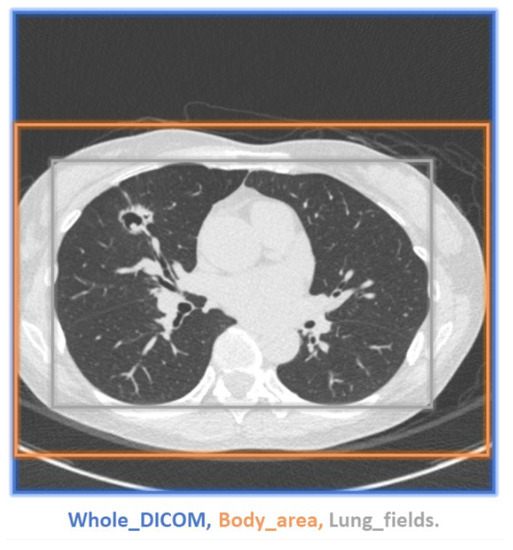

2.6. Quantitative and Statistical Analysis

A demonstration of the proposed method for selecting an ROI is presented in Figure 11. While the ROI covered the entire images (blue box), we also selected bounding boxes for the body area (orange box) and lung fields (grey box). Smaller bounding boxes ignored most of the ambient air and focused on the structures we were interested in. As expected, more uniform black ambient air areas increase the PSNR and SSIM. When the entire image was included in the calculation, the PSNR and SSIM values were relatively high, whereas the lung field bounding boxes yielded the lowest values (see Table 7 and Figure 12). Regardless, applying EDSR to the sagittal plane yielded the best results for all three ROIs (see Table 8). Overall, the PSNR and SSIM increased in the same manner, regardless of ROI selection (see Figure 13). One can see that EDSR was superior to the other models on average, but sometimes, SRResNet performs better than EDSR.

Figure 8. Generating desired ROI. (a) Body area; (b) Lung fields.

Figure 11. Demonstration of ROI selection. Blue box: whole DICOM image; Orange box: body area; Gray box: lung fields.